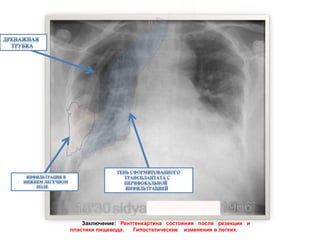

На обзорной рентгенограмме органов груднойклетки в прямой проекции, в условиях реанимации, положении сидя, 18/30 – состояние после операции – резекции и пластики пищевода. Легочные поля воздушные, легочной рисунок диффузно обогащен, инфильтрирован в нижнем легочном поле справа. Парамедиастинально справа тень сформированного трансплантата с перифокальной инфильтрацией. Тень сердца и крупных сосудов занимает типичное положение. Синусы справа свободны, слева завуалированы. В правой плевральной полости тени дренажных трубок. В динамике от 24.09.15 – без изменений. Заключение: Рентгенкартина состояния после резекции и пластики пищевода. Гипостатические изменения в легких.

Заключение: Рентгенкартина состоянияпосле резекции и пластики пищевода. Гипостатические изменения в легких.